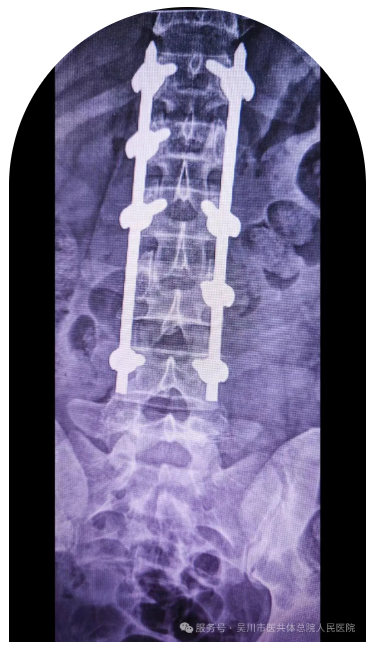

近日,63岁的沈女士不幸被大树砸伤,导致胸12椎体压缩性骨折,骨折块后突压迫椎管,相应脊髓受压变性,出现左下肢放射痛、麻木及肌力下降等症状,若不及时干预可能导致严重后遗症。

骨外科三区主任、主任医师曾维,主管医生宁健文迅速组织科室团队制定救治方案,决定为其实施 “胸12椎体骨折切开复位钉棒内固定术+后路减压术”。该科医护团队凭借丰富的临床经验与精准的操作技巧,成功复位骨折椎体、解除椎管压迫。

术后,沈女士左下肢放射痛、麻木症状逐渐减轻,肌力稳步恢复,看着身体一天天好转,她感慨道:“是曾主任和骨外科三区团队给了我重新站起来的希望!”